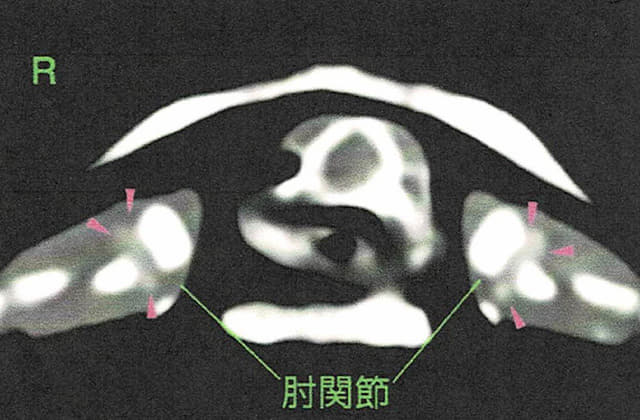

- 痛風は、関節の腫れが認められるレベルであればレントゲンで診断できるが、食欲が低下していても石灰化が軽度で、関節の腫脹も無い場合はCTでなければ診断が困難な場合もある

肘関節の石灰化

CT